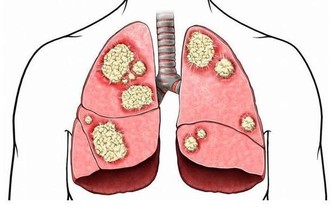

當肝臟腫瘤逐步增大,有可能會壓迫附近的橫膈膜,亦可壓著肺部以下的肌肉神經。而這些被壓著的神經正好是連接右肩的神經,就會引發右肩疼痛。所以,當出現反反复复的右肩膀疼痛時,經過適當的治療,症狀未能好轉,要及時檢查肝臟以排除存在的病變。